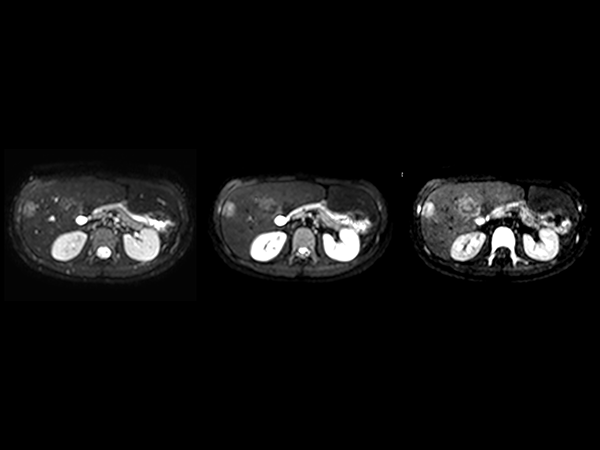

Axial Diffusion (b0, b50, b800)